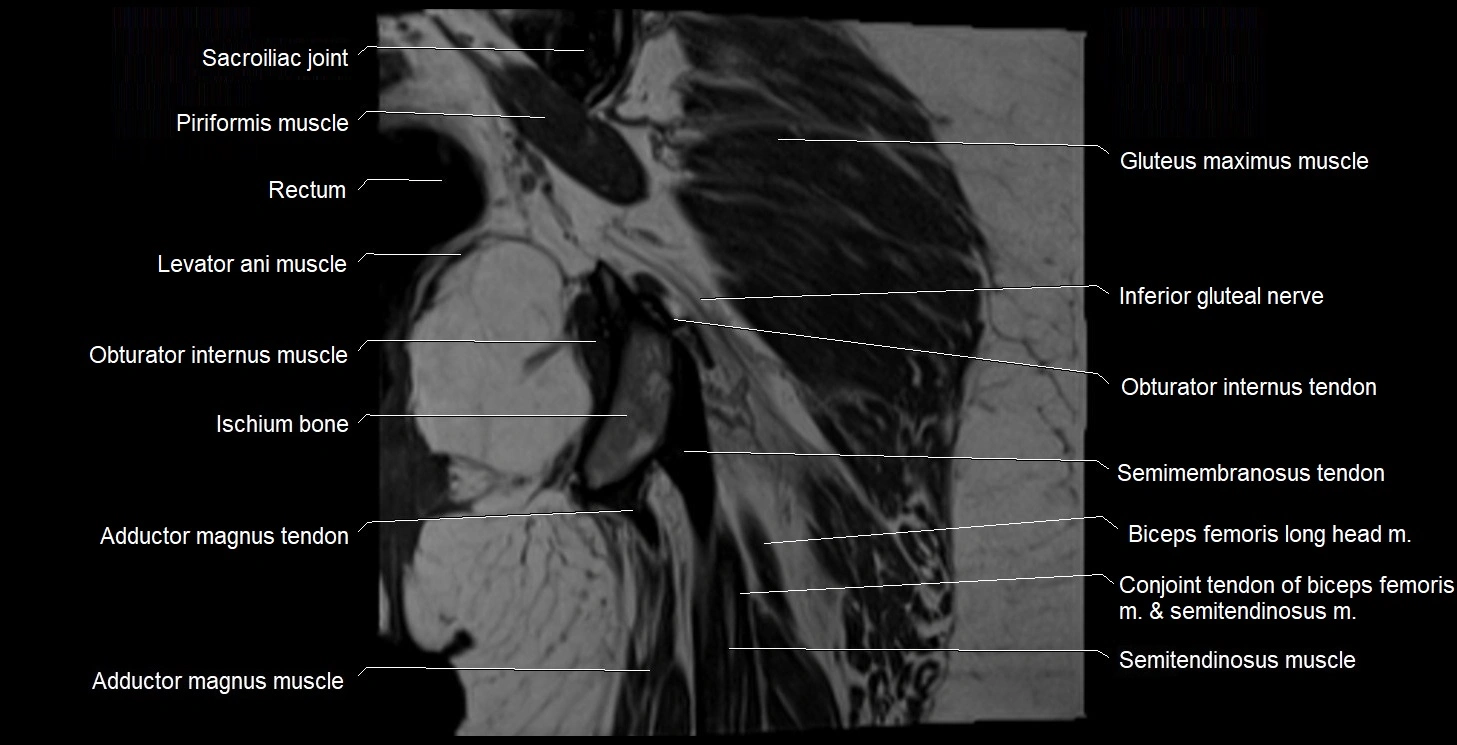

- Adductor magnus muscle

- Conjoint tendon of biceps femoris & semitendinosus

- Gluteus maximus muscle

- Ilium bone

- Ischial tuberosity

- Ischium bone

- Levator ani muscle

- Obturator internus muscle

- Obturator internus tendon

- Rectum

- Sacroiliac joint

- Semimembranosus tendon (proximal)